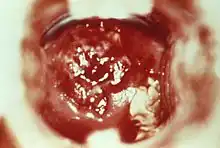

| HSV cervicitis | |

Cervicitis is inflammation of the uterine cervix.[1] Cervicitis in women has many features in common with urethritis in men and many cases are caused by sexually transmitted infections. Non-infectious causes of cervicitis can include intrauterine devices, contraceptive diaphragms, and allergic reactions to spermicides or latex condoms.[2] Cervicitis affects over half of all women during their adult life.[1]